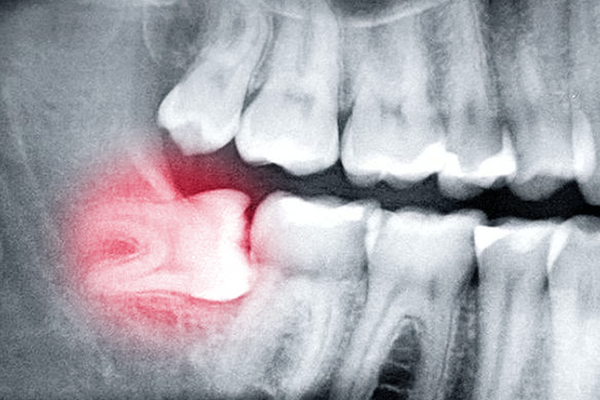

- Gây đau nhức: Răng khôn mọc lệch, mọc ngầm chèn ép các răng bên cạnh, gây đau nhức âm ỉ hoặc dữ dội.

- Viêm nhiễm: Răng khôn khó vệ sinh, dễ bị kẹt thức ăn, tạo điều kiện cho vi khuẩn phát triển, gây viêm nhiễm.

- Ảnh hưởng răng bên cạnh: Răng khôn mọc lệch có thể đâm vào răng số 7, gây sâu răng, lung lay răng.

- Biến chứng: Trong một số trường hợp, răng khôn có thể gây ra các biến chứng như u nang, tiêu xương.